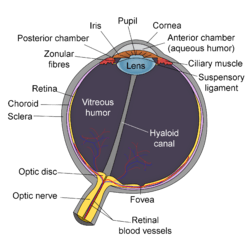

Schematic diagram of the human eye. | |

Structure

The lens is part of the anterior segment of the eye. In front of the lens is the iris, which regulates the amount of light entering into the eye. The lens is suspended in place by the suspensory ligament of the lens, a ring of fibrous tissue that attaches to the lens at its equator[1][2] and connects it to the ciliary body. Posterior to the lens is the vitreous body, which, along with the aqueous humor on the anterior surface, bathes the lens. The lens has an ellipsoid, biconvex shape. The anterior surface is less curved than the posterior. In the adult, the lens is typically circa 10 mm in diameter and has an axial length of about 4 mm, though it is important to note that the size and shape can change due to accommodation and because the lens continues to grow throughout a person's lifetime.[3]

The lens has three main parts: the lens capsule, the lens epithelium, and the lens fibers. The lens capsule forms the outermost layer of the lens and the lens fibers form the bulk of the interior of the lens. The cells of the lens epithelium, located between the lens capsule and the outermost layer of lens fibers, are found only on the anterior side of the lens. The lens itself lacks nerves, blood vessels, or connective tissue.[4]